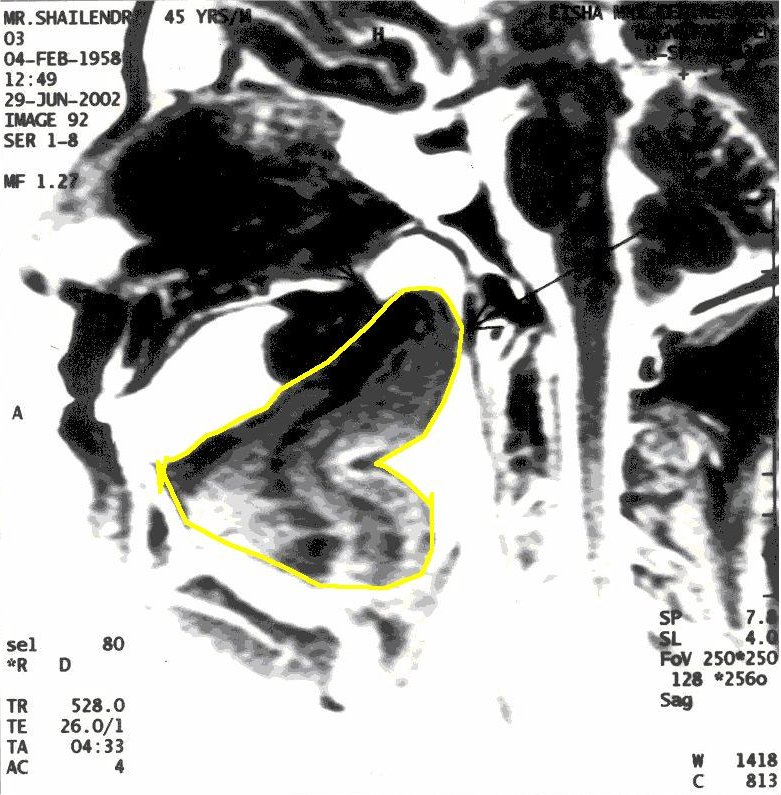

MRI of Yogiraj Shailendra Sharma in Khechari Mudra

With Khechari Mudra – The position of tongue is outlined in yellow